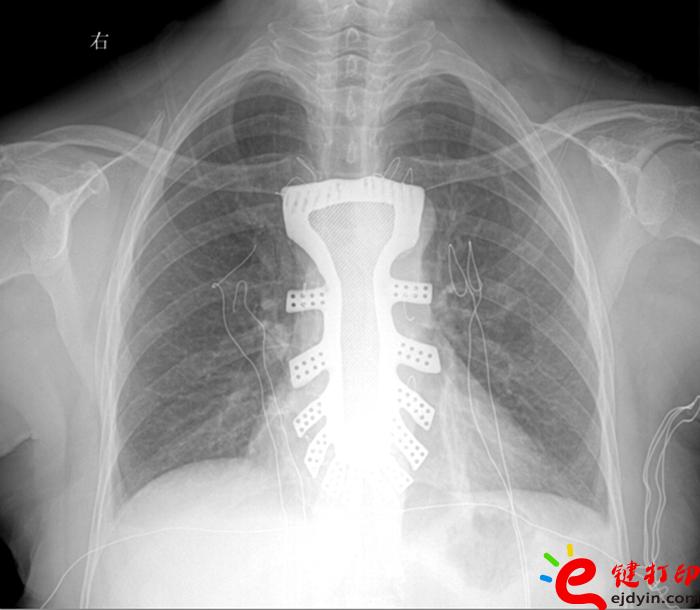

據王小平教授介紹,唐都醫院3D打印小組經過精密計算患者胸骨的大小、形狀等,充分研究討論,歷時一周,為患者設計出了手術使用的3D胸骨模型,并與西北工業大學凝固技術國家重點實驗室合作,為患者打印出了1:1鈦合金胸骨模型。隨后,又對該模型進行了一系列嚴密的醫學處理。

“手術歷時2.5小時,對患者的胸骨進行了整體切除,置換了鈦合金胸骨,目前患者恢復良好,未發現任何并發癥?!蓖跣∑浇淌诜Q,根據專業機構檢索,該手術是世界首例針對胸骨腫瘤疾病,將3D打印的可植入性鈦合金胸骨植入人體,實現病變胸骨的整體置換的手術。該手術的成功意味著未來將會為更多的胸骨腫瘤患者帶來福音。

參與此次3D鈦合金胸骨設計的唐都醫院3D打印團隊王臻博士表示,此次嘗試是3D打印技術與外科手術的一次完美結合。3D打印的個性化服務與醫學有著天然的聯系,目前3D打印技術在醫學上的研究越來越廣泛,為醫學的未來發展提供了無限可能。